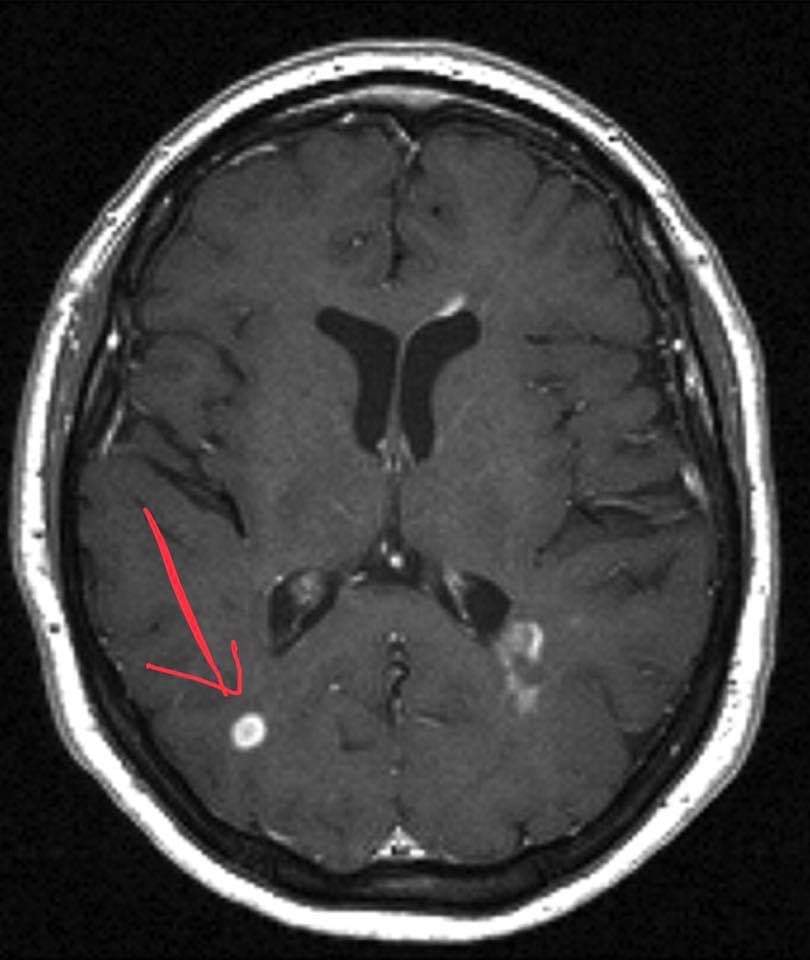

خلال انتكاسة أو هجمة التصلب اللويحي، يحدث هجوم مناعي على الجهاز العصبي، خاصة على غشاء المايلين والذي بدوره يؤدي لالتهاب المايلين، وبالتالي تفاقم الأعراض السابقة أو ظهور أعراض جديدة.